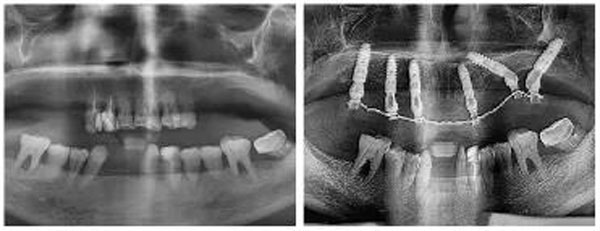

經過全面的檢查和細致的溝通,新橋光華店種牙團隊為鄧女士量身定制了半口即拔即種-即刻負重修復方案,通過在上頜種植6顆植體,即可恢復12顆牙齒的咀嚼功能。面對超出預期的治療費用,夫妻倆斷然拿出了自己房子的部分裝修款。而這樣堅決的原因,余先生用自己瀟灑的人生態度做了最好的注解。

鄧女士種牙前后全景片對比